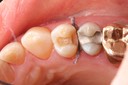

Mark Chun #17 pre-op